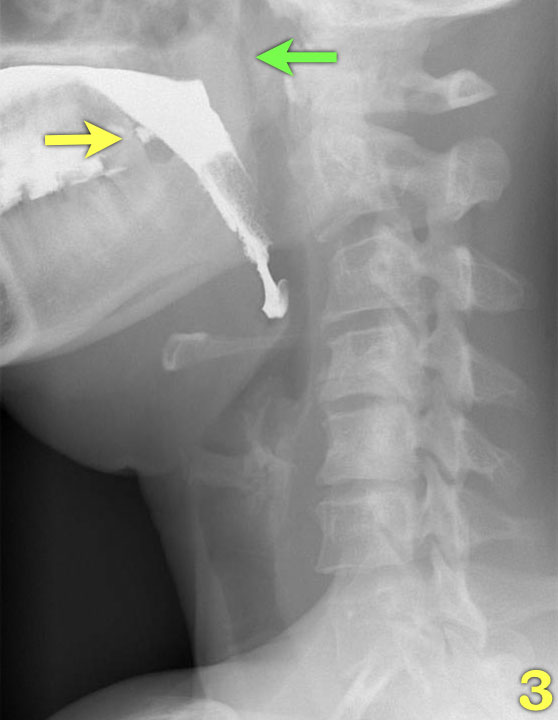

- Sự co thắt của cơ khít hầu giữa (mũi tên vàng), trong khi cơ nhẫn hầu đã giãn hoàn toàn (mũi tên xanh lá).

- Sự co thắt của cơ khít hầu dưới làm tống xuất hầu họng.

- Nắp thanh thiệt nâng lên để trở về vị trí nghỉ và thanh quản mở ra (mũi tên).

- 1-3. Không thấy co bóp của thành sau hầu họng. Cơ nhẫn hầu không mở đúng cách.

- 4-7. Thuốc cản quang vào thanh quản nhưng không vào khí quản.

- 8-10. Cử động đầu quá mức nhằm đẩy bolus vào thực quản.